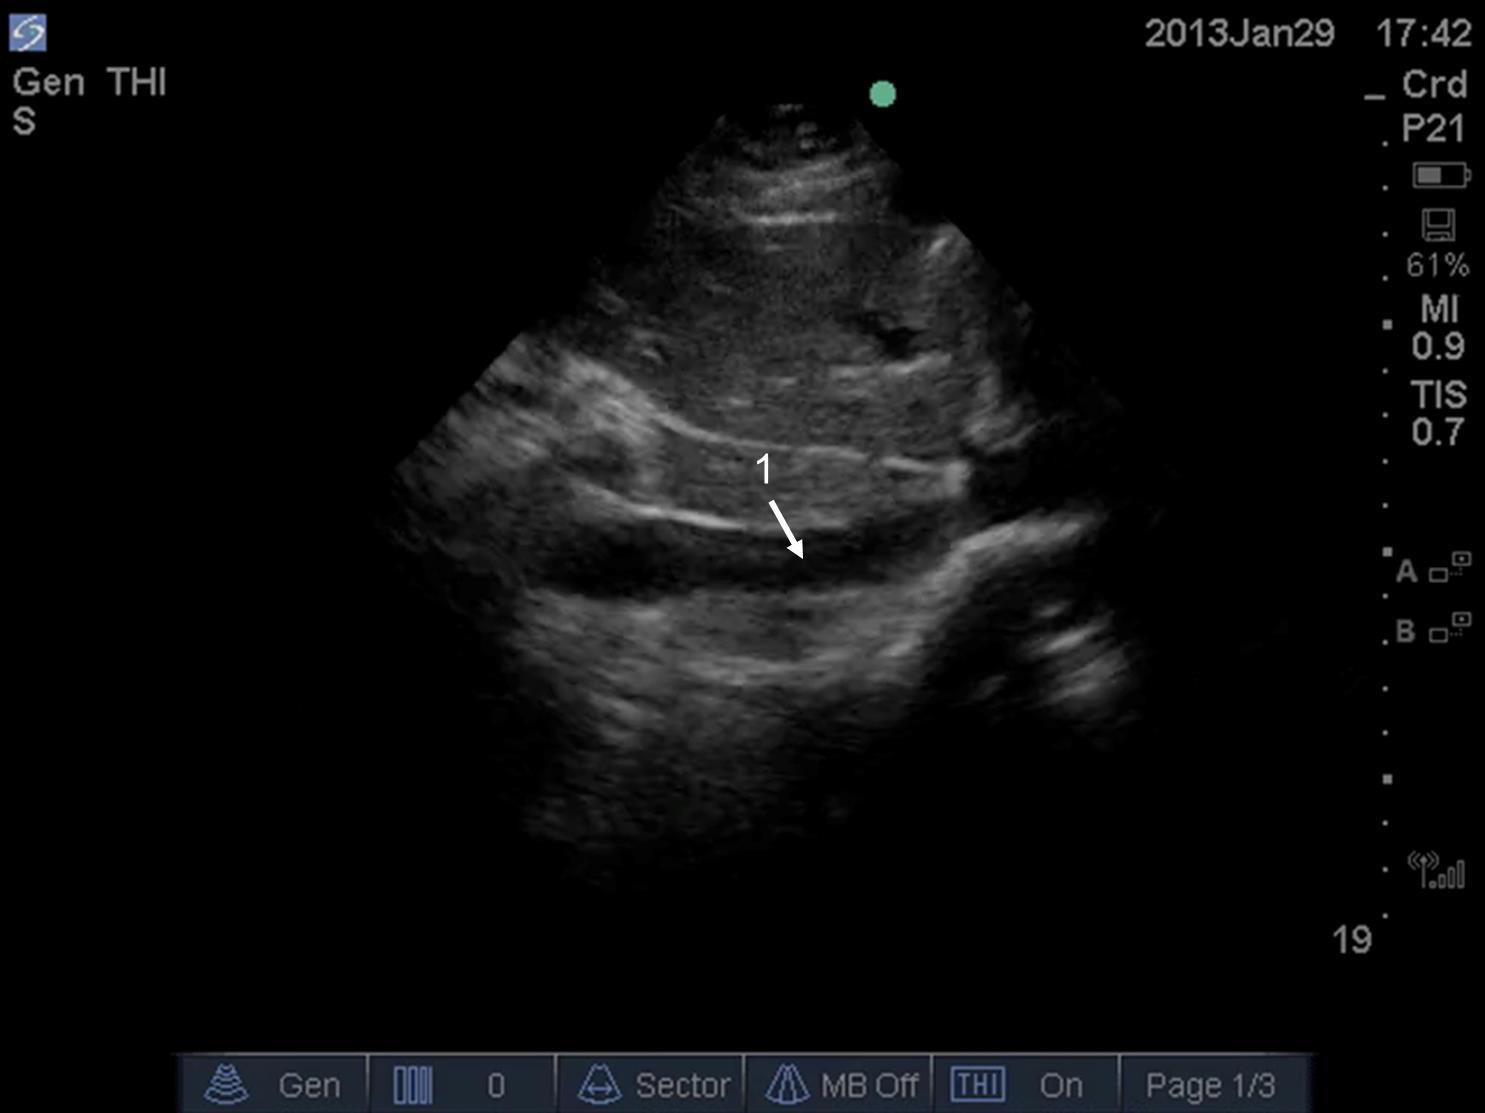

Inferior Vena Cava (IVC) Passive Patient on Ventilator Image

Distention